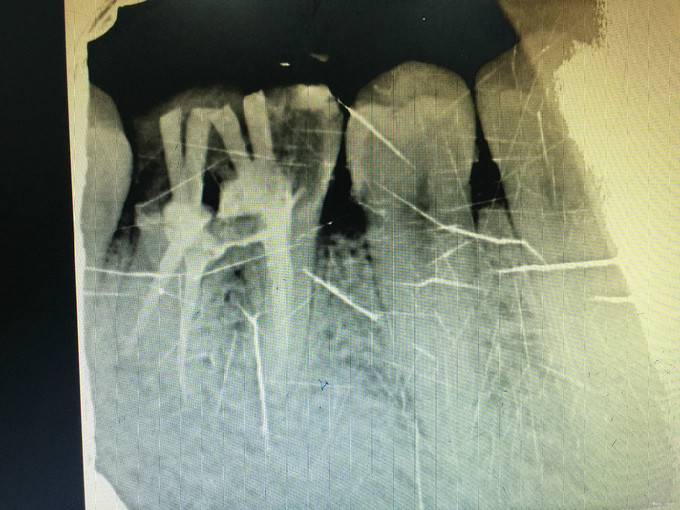

临床检查:46充填物未脱落,探疼(+—),冷(—),叩(+),松动度(-),牙周正常. 辅助检查:X线示46充填物累积髓腔,根尖周牙周膜略增宽。

诊断:46慢性牙髓炎 治疗:经患者知情同意后,46局麻去除原有充填物降牙合,开髓寻找根管口,建立直线通路,扩通根管,确定工作长度。S3/EDTA凝胶镍钛器械,低浓度次氯酸钠冲洗根管,预备至35/04,氢氧化钙诊间封药,一周后复诊,试主尖X线示恰充,试干根管,导AH-PLUS糊剂,VDW热压胶垂直加压根充,术后见根管恰充,暂封调合抛光。